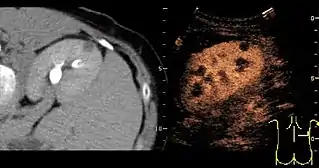

- Lesion Characterization: contrast-enhanced ultrasound plays a role in the differentiation between benign and malignant focal liver lesions. This differentiation relies on the observation[15] or processing[16][17] of the dynamic vascular pattern in a lesion with respect to its surrounding tissue parenchyma.

- Sulphur hexafluoride microbubbles (SonoVue Bracco (company)). It is mainly used to characterize liver lesions that cannot be properly identified using conventional (b-mode) ultrasound. It remains visible in the blood for 3 to 8 minutes, and is expired by the lungs.[9]